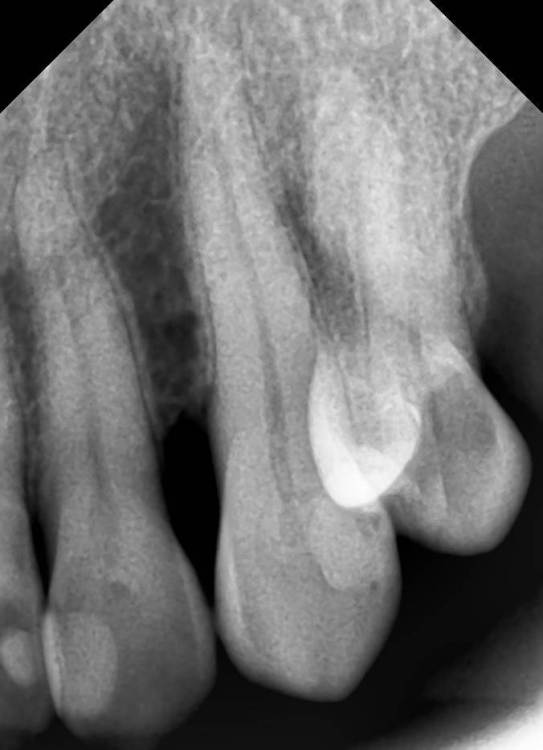

Никка Опубликовано 4 марта, 2024 Поделиться Опубликовано 4 марта, 2024 Здравствуйте! Прошу совета в моей ситуации, благо есть замечательные медицинские ресурсы. Кратко: на десне между 2 и3 верхними 3 недели назад появился отек и покраснение, я посчитала, что проявления гингивита (такое периодически бывало в течение последнего полугода). Полоскания-мазилки не помогли. появился гнойник, который самостоятельно вскрылся через неделю. 2 недели было все ок, сейчас опять ощущение, что начинается - некоторое покраснение, небольшой отек, чувство распирания. Была у терапевта, проверили зубы - живые. Сделан снимок и 3d КТ. На них криминала вроде как не обнаружено. Направили к парадонтологу с целью выяснить, надо ли делать открытый кюретаж. Пока ждала записи, десна стала обычной, кроме ямочки (свищ?) ничего. Сказали, пока делать нет смысла. Но сейчас опять беспокоит. Что вы посоветуете? Прикрепляю фото самого абсцесса в момент пика, снимки. Спасибо! Ссылка на комментарий